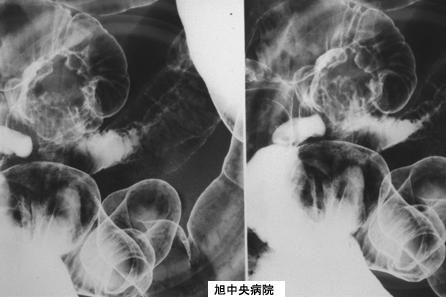

A case of ileal endometriosis with ileus symptoms.

Chiba Pref., National Asahi Central Hospital

Tumor-like lesions/Endometriosis

Location

Small intestine/Jejunum

X-ray

35 - 40